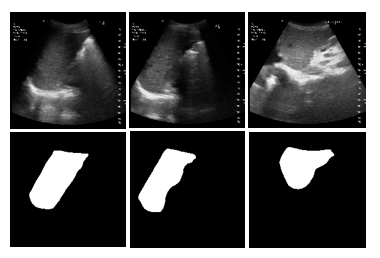

US Liver Segmentation Results: We used FCN [10], UNet [13], UNet++ [20] with EfficientNetB7 encoder, and TransUNet [2] for segmenting US scans for US liver segmentation (Table 1). TransUNet achieved the best Accuracy (Acc.), Dice Score Coefficient (DSC), Intersection over Union (IoU), and Hausdorff distance (HD) for unseen data. This is because TransUNet uses transformers to encode tokenized image patches from a CNN feature map. Thus, the input sequence captures global contexts [2]. We used UNet as the decoder to decode the hidden feature for generating the final segmentation masks. 2D liver predictions overlap well with ground truth liver labels. This, in turn, leads to an accurate liver volume calculation. Ours is the first method that uses a transformer network in US liver segmentation. Following this result, we used TransUNet for all other experiments.

Figure 2: US segmentation and 3D reconstruction results: Three input US sagittal plane images, corresponding segmentations, and 3D liver reconstructions using the shape parameters for three subjects.

Table 1: Segmentation accuracy: TransUNet performs better and, hence, was selected for subsequent experiments. \ast represents the usage of EfficientNet-B7 as an encoder. 3D reconstruction accuracy: CD and MSD are less when we combine TransUNet with Param. Regress. MLP than UNet.

Segmentation FCN UNet UNet++\ast TransUNet

Acc. (%) \uparrow 93.2 95.4 94.4 97.5

DSC (%) \uparrow 38.5 65.6 68.1 91.3

HD (mm) \downarrow 5.5 4.8 4.5 3.6

IoU (%) \uparrow 24.1 50.2 52.7 84.4

Recon. TransUNet UNet

Accuracy + Recon. + Recon.

MSD (mm)\downarrow 6.6 6.8

CD (mm) \downarrow 12.8 13.1